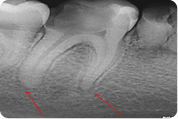

Kronične upale kosti uglavnom su bezbolne, a često se otkriju kao slučajni nalaz na rtg snimci. Ponekad kronični proces u kosti oko vrha korijena, koji se često naziva granulom, prijeđe u akutni oblik sa svim njegovim simptomima. Ponekad se kod kroničnih oblika pojavi fistula kao put dreniranja gnojnog procesa iz kosti. To pacijenti često opisuju kao vrećicu koja se puni i povremeno prazni.

Sam postupak endodontskog liječenja započinje postavljanjem dijagnoze kliničkim pregledom i rtg snimkom. Rtg snimanje je obavezno prije samog liječenja jer se njime vide uzroci bolesti, postojanje eventualnog procesa u kosti te ono što je jako važno za samo liječenje, broj korjenova i kanala, zakrivljenost i druge njihove morfološke varijacije. Time se doktoru dentalne medicine omogućuje orijentacija u prostoru korijenskih kanala. Na osnovu rtg snimke doktor dentalne medicine može ocijeniti postoji li uopće mogućnost liječenja te predvidjeti moguće poteškoće u postupku.

Nakon završenog liječenja, kvaliteta punjenja se provjerava rtg snimkom čime se procjenjuje dužina i kompaktnost punjenja. Tek ako je rentgenogram potvrdio dovoljno kvalitetno punjenje, zub se rekonstruira bilo ispunom ( "plombom" ) ili protetski ( nadogradnja i krunica ).

U slučaju postojanja periapikalnog procesa ( granuloma ) zub se ponovno kontrolira nakon šest mjeseci, nakon godinu, odnosno dvije godine. Uspješnost liječenja se procjenjuje na temelju cijeljenja granuloma koji nestaje na čijem mjestu se stvara nova kost. To dovodi do odgovora na pitanje koje se često postavlja doktoru dentalne medicine:"Je li moguće liječiti granulom liječeći zub?" Odgovor je: "Svakako da, jer su uzrok granulomu iritansi iz korijenskog kanala. Kad se oni uklone, organizam sam zacijeli oboljelo tkivo".